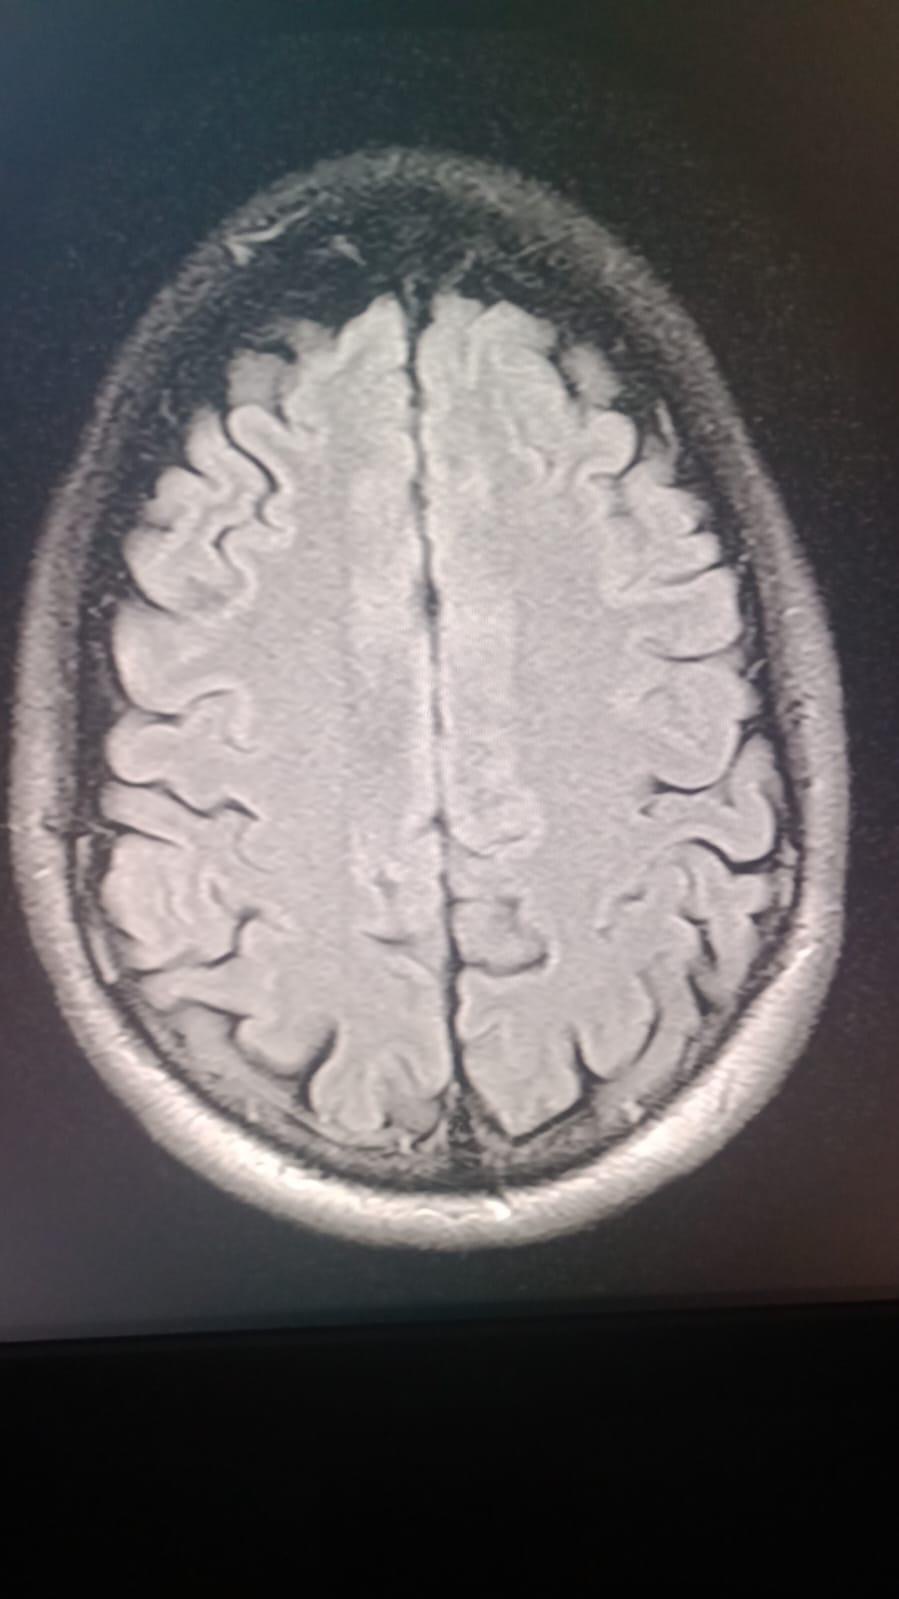

Our dear Cesar Eduardo Rodríguez Ortiz has been fighting seizures since he was just two years old, after suffering a head injury as a baby. Despite years of struggle, his strength and spirit have never faded.

On October 17, 2025, Cesar underwent a major brain surgery to help control his severe epilepsy. By God’s grace, the surgery went well, and he is now beginning his road to recovery.